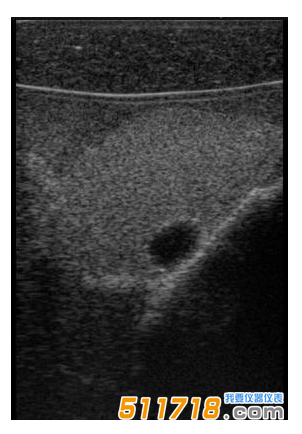

CIRS 074甲狀腺超聲訓練模體包含一個略微擴大的甲狀腺,位于一個擬人化的頸部。下巴和鎖骨被提供作為外部解剖標志。體模提供氣管,頸內靜脈和頸總動脈作為內部解剖標志。每個甲狀腺葉包含一個囊腫和一個等回聲僵硬病變。可以在甲狀腺內定制生產各種結節。*有材料都配制成超現實的。

可以對每個囊腫進行細針抽吸。每個僵硬病變都設計用于超聲彈性成像的可視化,并且可以進行活組織檢查。這些病變對甲狀腺是等回聲的并且具有標準的B模式成像。

單純囊腫